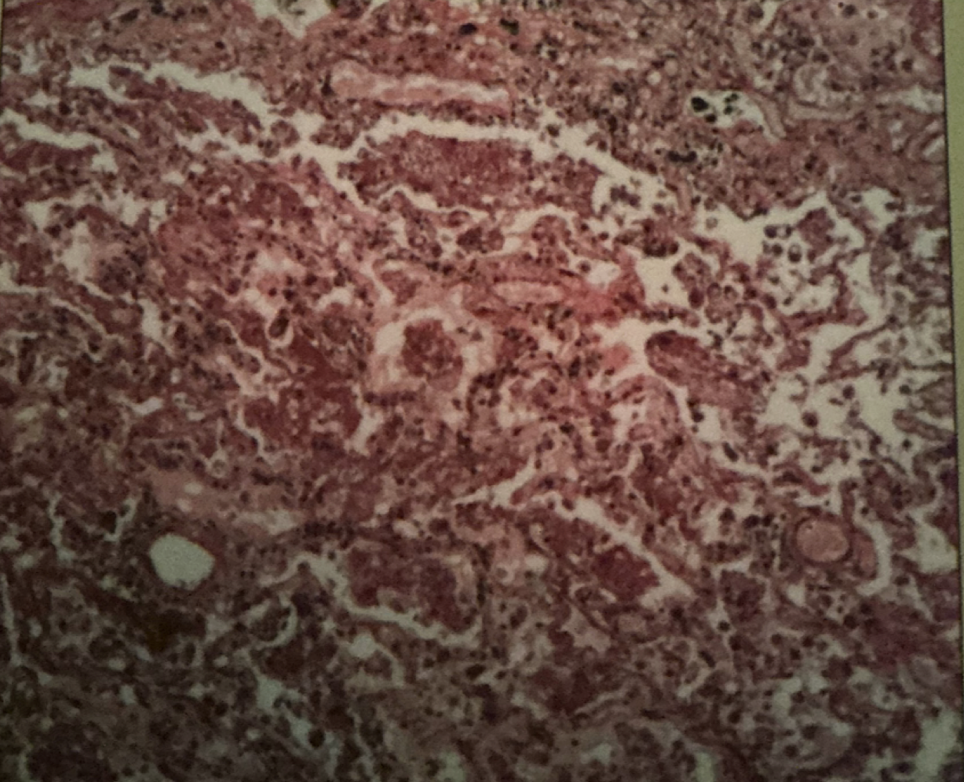

emphysema

emphysema

breakage & collapse of alveoli —> reduction of SA fro gas exchange and O that reaches bloodstream